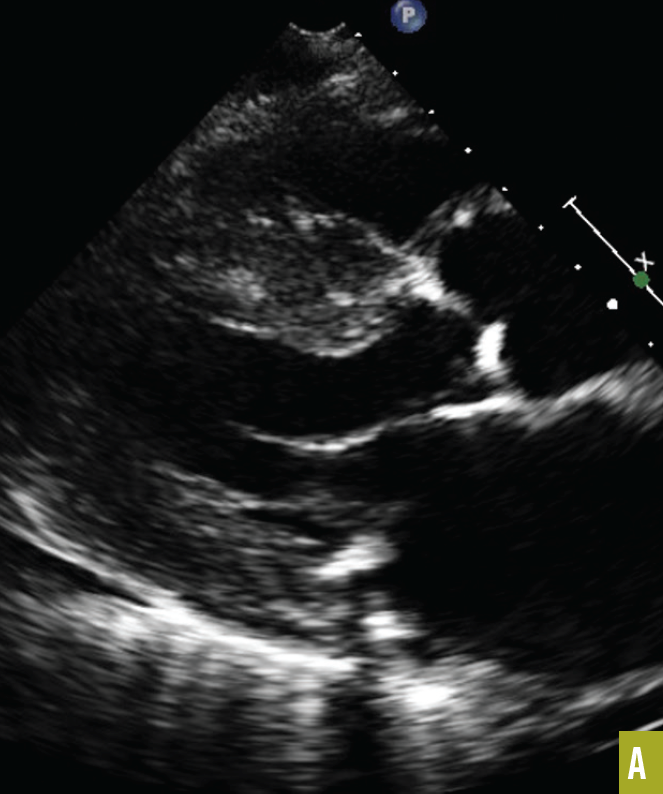

Ronald N. Rubin, MD

A 60-year-old man sustained an acute myocardial infarction (AMI). A brief summary of his history revealed that he was a classic case of metabolic syndrome, with obesity, type 2 diabetes mellitus, and...